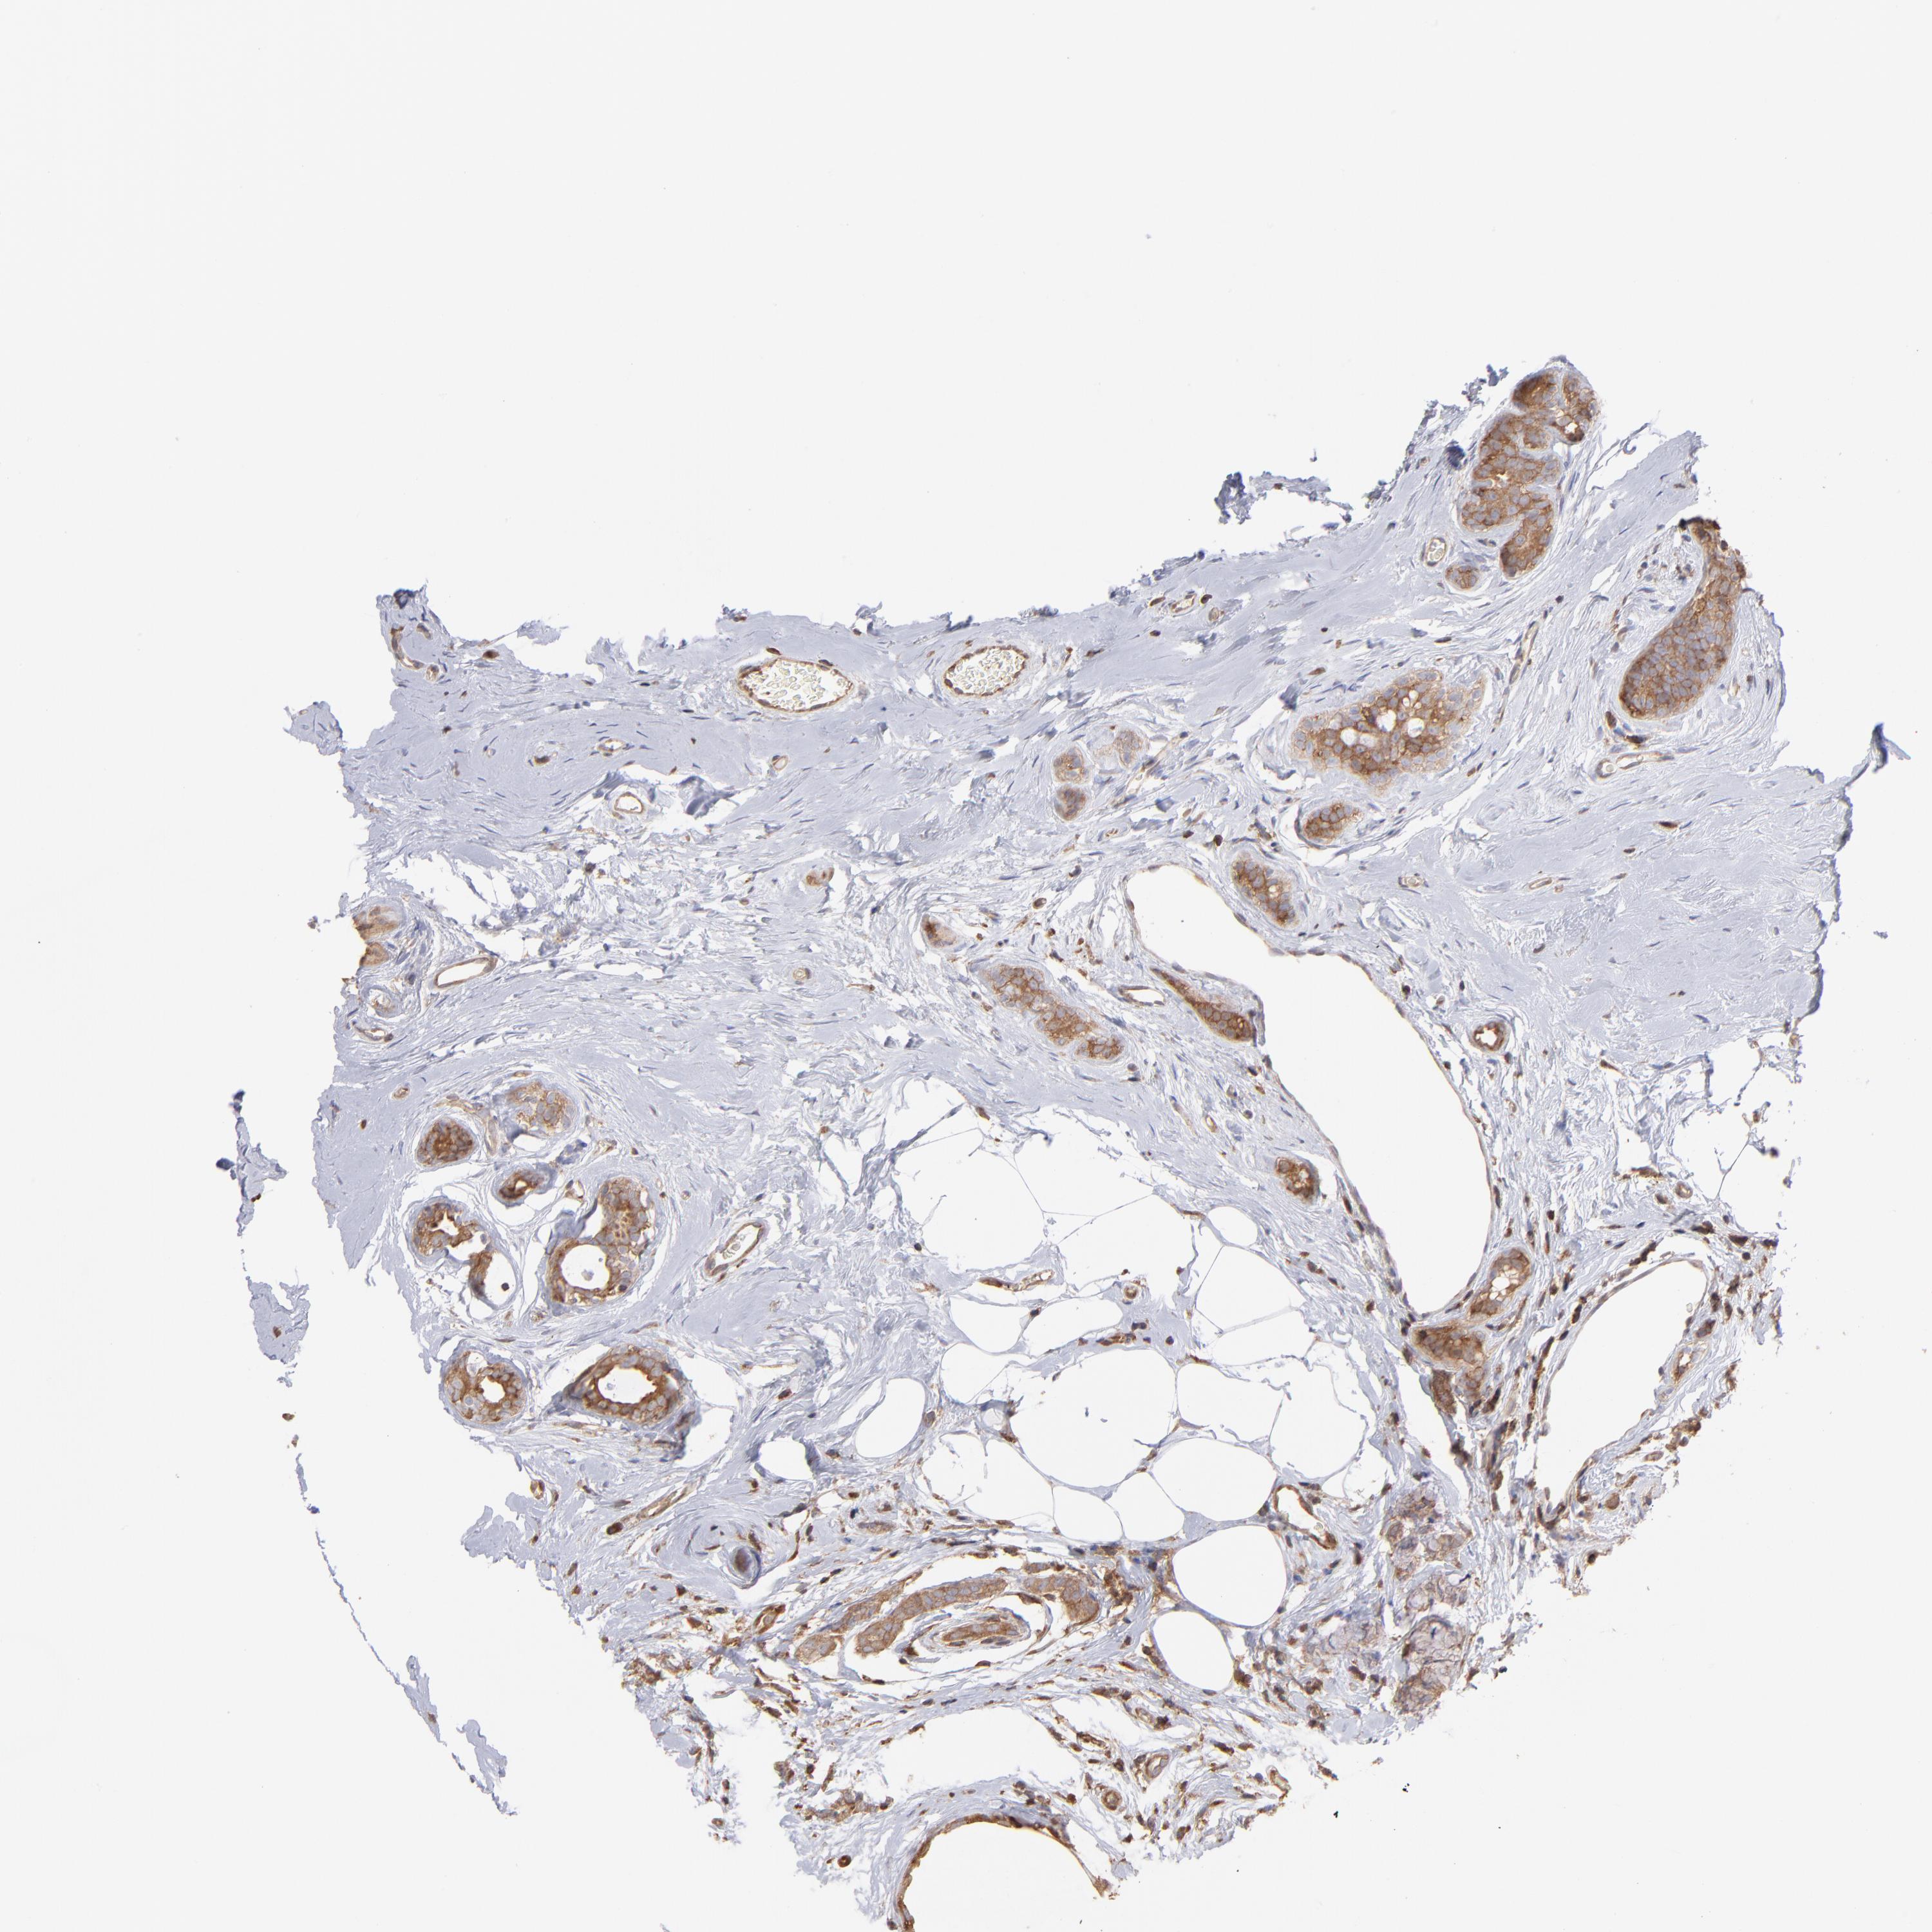

BRCA TCGA BRCA VALIDATION PROTEIN EXPRESSION